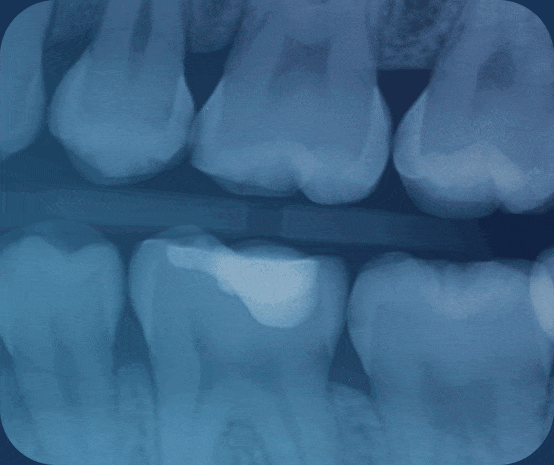

AI-Powered Radiologic Platform

The first real-time, FDA-cleared dental AI platform that automatically detects numerous conditions in dental x-rays to give dentists a second set of eyes for superior radiologic accuracy and improving clinical outcomes.

PEARL SECOND OPINION®